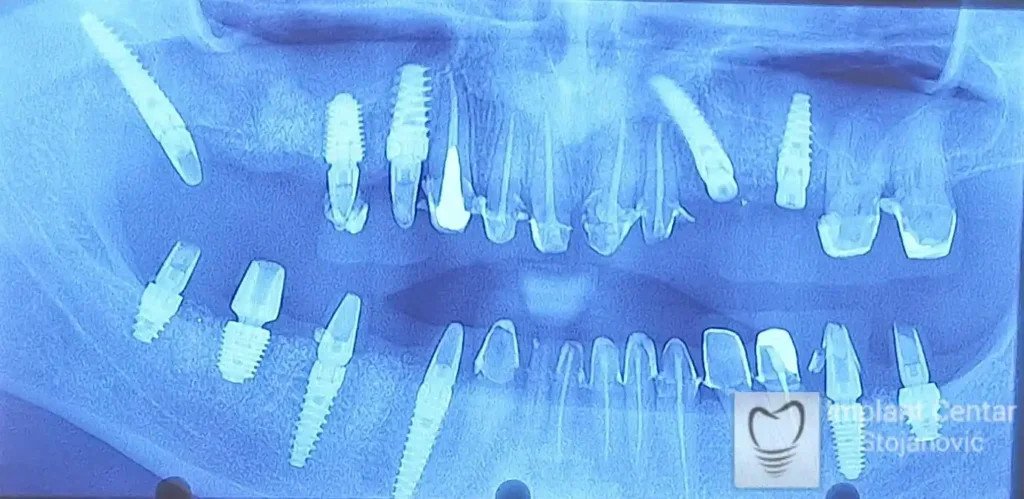

Na slici 1. i slici 2. prikazan je izgled pacijenta pre početka terapije – klinički i rendgenološki.

Nakon vađenja zuba, ugrađeni su implantati. Na slici 3 prikazan je ortopan snimak sa ugrđenim implantatima. Tokom perioda osteointegracije, pacijent je bio zbrinut fiksnim privremenim krunicama na implantatima, koje su izrađene samo dva dana nakon hirurške intervencije.